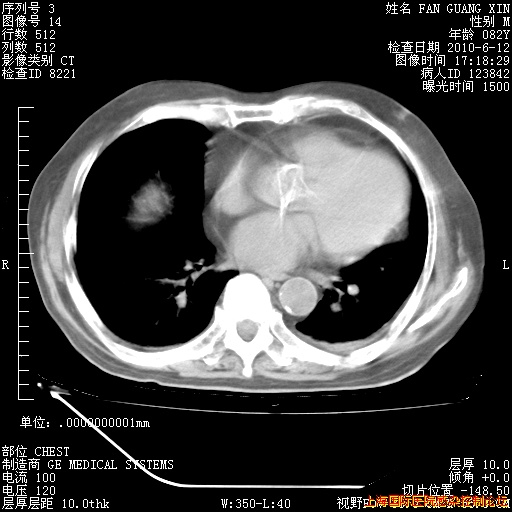

今天复查CT

今天CT

整整相隔30天的肺部CT好像有所好转啊。甲强龙减量第3天,需要观察体温。

海管,自昨日你和我通完话后,不知您岳父消化道症状有无缓解?体温怎样?阅读7.12日胸部ct,个人认为目前激素治疗是有效的,甲强龙减量是适宜的。因在抗痨治疗,需密切观察肝功、肾功能和血常规。不过,老年、长期住院和大量使用激素,很担心菌群失调发生